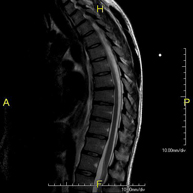

Prova diagnòstica no invasiva que consisteix en l'obtenció d'imatges d'alta definició anatòmica de la columna cervical mitjançant l'ús d'un camp electromagnètic i ones de ràdio (com un emissor i un receptor). No utilitza radiació ionitzant. Indicacions: traumatisme, degeneració de la columna, hèrnies. - RM de columna dorsal

Prova diagnòstica no invasiva que consisteix en l'obtenció d'imatges d'alta definició anatòmica de la columna dorsal mitjançant l'ús d'un camp electromagnètic i ones de ràdio (com un emissor i un receptor). No utilitza radiació ionitzant. Indicacions: traumatisme, problemes degeneratius, hèrnies, tumors. - RM de Columna lumbar

Prueba diagnóstica no invasiva que consiste en la obtención de imágenes de alta definición anatómica de la columna cervical mediante el empleo de un campo electromagnético y ondas de radio (con un emisor y un receptor). No utiliza radiación ionizante. Indicaciones: traumatismo, degeneración de la columna, hernias. - RM Columna Dorsal

Prueba diagnóstica no invasiva que consiste en la obtención de imágenes de alta definición anatómica de la columna dorsal mediante el empleo de un campo electromagnético y ondas de radio (con un emisor y un receptor). No utiliza radiación ionizante. Indicaciones: traumatismo, problemas degenerativos, hernias, tumores. - RM Columna Lumbar